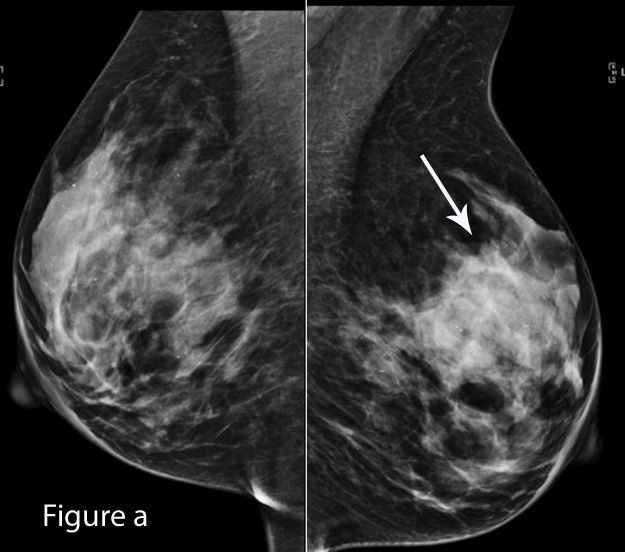

On mammography (a-b), a 1-cm spiculated mass (arrow) was identified within the left breast, best demonstrated on the lateral view (c). Ultrasound (d) demonstrated an 8-mm hypoechoic mass in the 10:00 position of the left breast and, in addition, ultrasound identified a 1.1-cm hypoechoic mass at the 1:00 position (e). A needle core biopsy of the 10:00 mass was performed resulting in a diagnosis of invasive ductal carcinoma. The patient was referred for breast magnetic resonance imaging (MRI) for extent of disease evaluation. Breast MRI (f) demonstrated a new enhancing mass in the contralateral breast. MRI of the ipsilateral breast (g) demonstrated two enhancing masses consistent with the two lesions identified on ultrasound. Biopsy of new lesion in the contralateral breast was recommended.